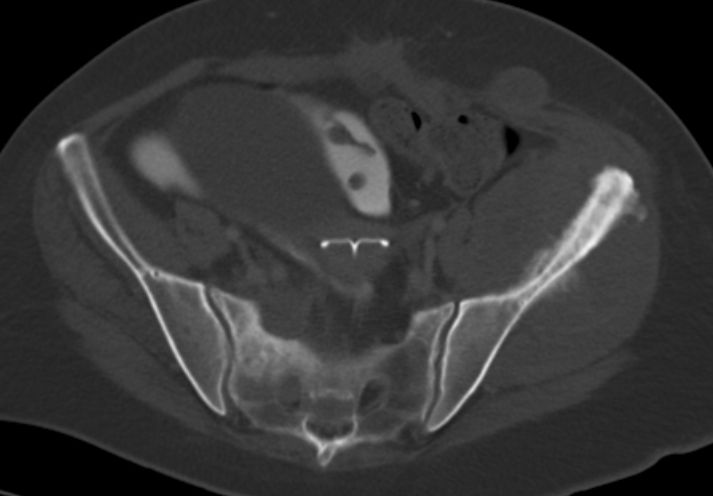

51-jährige Frau, bei der vor 4 Jahren ein Colon-ascendens Karzinom im Stadium pT3d N0 (0/20) L0 V0 G2 mit Hemicolektomie behandelt wurde.

K-RAS - Mutation vorhanden. Adjuvant Capecitabin.

Vor 4 Jahren Ovarialmetastasen: OP, dann FOLFIRI.

Vor 3 Jahren Resektion von Bauchdeckenmetastasen.

Vor 2,5 Jahren Resektion von inguinalen LK-Metastasen und Hautmetastasen. Post OP Bevacizumab/FOLFIRI.

Vor 2 Jahren Lebermetastasen.

Jetzt Schmerzen im linken Becken und Gesäß. Metastase der linken Beckenschaufel mit großem Weichteiltumor.

Im Knochenfenster.